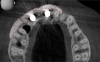

The intraoral examination revealed a substantial deficit of alveolar bone and gingival tissues in the maxillary right lateral incisor area. The ridge defect exhibited vertical and horizontal components, which were associated with a severe loss of clinical attachment on both the mesial aspect of tooth No. 6 and the distal aspect of tooth No. 8. Although probing depths were within normal limits, minimal keratinized gingiva was present and the soft tissues were acutely inflamed. Plaque removal was difficult because of the soft-tissue defect, gingival-margin location, and irregular soft-tissue architecture. Additionally, bone sequestration could be observed through the labial mucosa (Figure 2).

Fig 2. A failed implant and bone-graft procedures had resulted in a substantial iatrogenic gingival-alveolar defect.

Figure 2